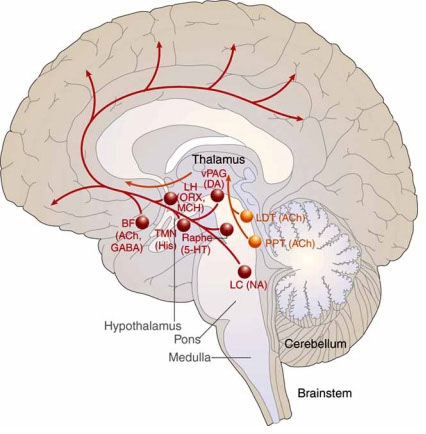

7e) Neurological Effects of Apnea

Emerging science can help explain the link between excessive daytime sleepiness (EDS) and OSA

- EDS is one of the most common symptoms of obstructive sleep apnea (OSA)

- Animal and human studies suggest that the recurring cycle of intermittent hypoxia and sleep fragmentation associated with OSA may result in changes to the brain

- The subsequent disruption in neurologic function + may manifest as excessive sleepiness during the day

- While brain alterations have been linked to sleepiness, persistent EDS may be due to other factors such as chronic sleep loss and coc disorders1"

In an animal model of severe sleep apnea, chronic intermittent hypoxia led to significant neuronal injury'

Long-term hypoxia significantly increased oxidative injury to wake-promoting dopaminergic and noradrenergic neurons compared with the control group (Pc-0.01)2*

The loss of medial dendrites represents irreversible and functionally significant injury to wake-promoting regions of the brain'

At 6 months, a 40% JOSS of select wake-promoting dopaminergic and noradrenergic neurons was associated with irreversible wake impairments'

In a separate animal model of OSA, chronic sleep fragmentation led to a significant loss of wake-promoting neurone

Exposure to sleep disruptions over 14 weeks caused a significant reduction of wake-promoting noradrenergic neurons compared with the control group (P<0.001), even after 4 weeks of recovery'

Excessive daytime sleepiness (EDS) in OSA is associated with significant changes to the brain

Obstructive sleep apnea (OSA) is associated with reduced gray matter concentration"

Imaging studies in patients with severe OSA showed reduced gray matter concentration in certain brain regions compared with healthy volunteers, including the frontal cortex, anterior cingulate cortex, and thalamus.''

Some of these regions are involved in wakefulness and neurocognitive performance in' • Problem-solving • Planning • Decision-making • Attention/concentration

EDS in OSA is associated with significant white matter structural alterations despite the optimal use of CPAP'

Widespread white matter changes were observed in patients with OSA-associated EDS despite optimal CPAP adherence hours for 1 month) vs nonsleepy patients'

These changes ideate potential myelin damage and compromised neuronal connectivity'

This may help explain why EDS can persist in patients with OSA, even with optimal CPAP use?